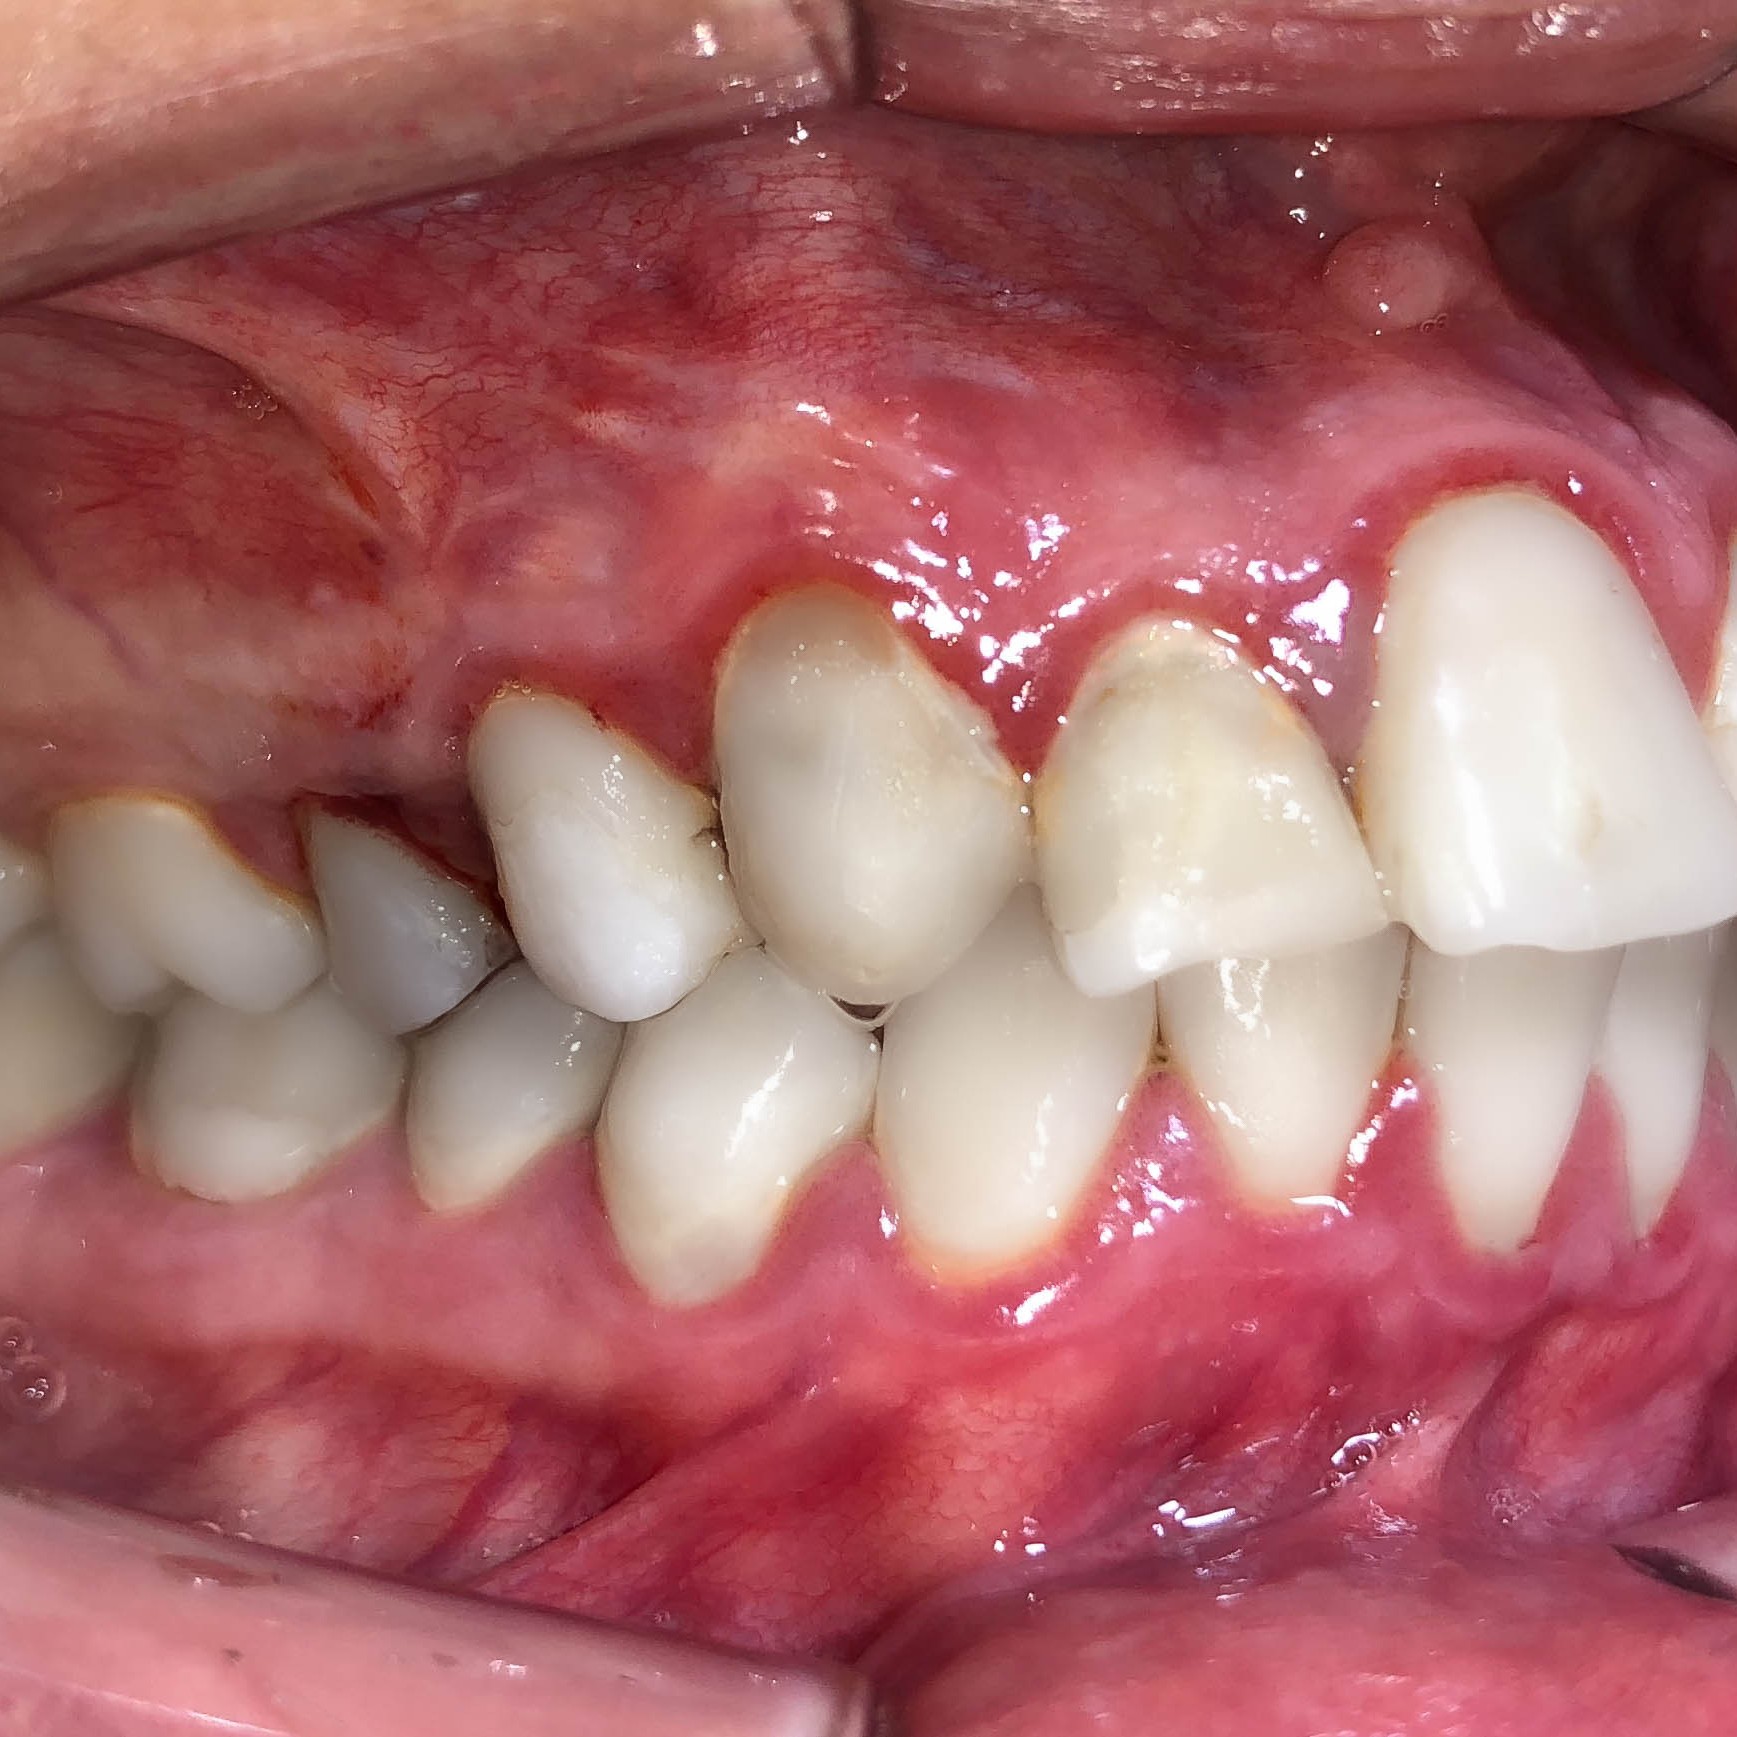

Zahntaschenbehandlung / Parodontologie

Der Zahn ist in einem Knochenfach verankert/aufgehangen. Dabei gibt es einen kleinen Spalt zwischen Zahn und Knochen. Dieser nennt sich Paradontalspalt und bietet einigen speziellen Bakterien die Möglichkeit sich dort zu vermehren. Eine solche Entzündung kann ohne jegliche Schmerzen über Jahre oder Jahrzehnte ablaufen. Ein Verdacht für die im Volksmund benannte „Parodontose“ können Mundgeruch und oder Zahnfleischbluten sein. Auch genetische Veranlagungen sind dafür verantwortlich, dass manche Patienten davon mehr betroffen sind als Andere. Bei richtiger Diagnose kann zeitnah mit einer Therapie begonnen werden und um diesen entzündlichen Prozess des Knochenabbaus zu verlangsamen oder gar zu stoppen.